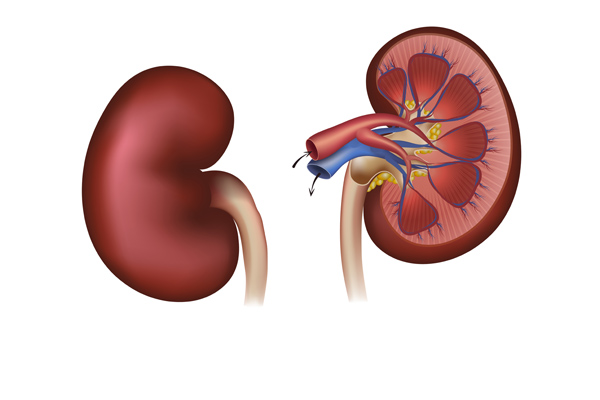

Our kidneys are incredible organs that get rid of toxins, retain substances needed by our bodies, and maintain the right balance of...